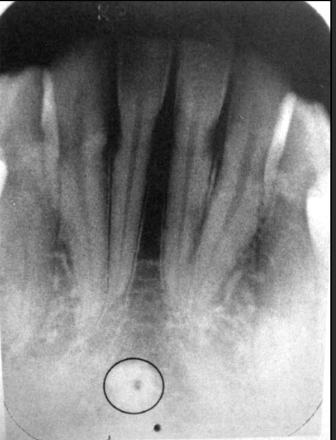

How does the genial tubercles/mental spines present in a radiograph?

Presents as a ring shaped radio opacity (white donut). Sits below the centrals on the mandible. It is the white portion. The radiolucent dot is a different structure

How does the lingual foramen present in a radiograph?

Presents as a tiny radiolucent dot below the mandibular centrals. Looks like a white donut because it is overlapping with the genial tubercle.